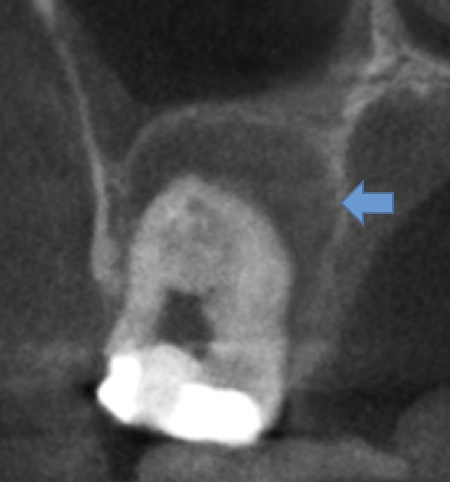

かぶせ物が不適であること(青矢印部)、近心根に根尖病巣があること(青枠部)、根充剤がかなり太いため(赤矢印部)歯質が薄くなっていることなど問題点がいくつかありましたが、他院で治療をしたばかりであり、また上記の条件から再治療には抜歯のリスクが非常に高いことから初診時は患者さんと相談し経過観察することになりました。